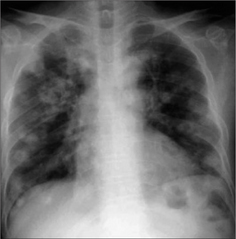

Figure 21.2 Multiple nodules. Metastases from a renal cell carcinoma. The appearances are typical of metastases–rounded lesions with fairly well-defined margins.